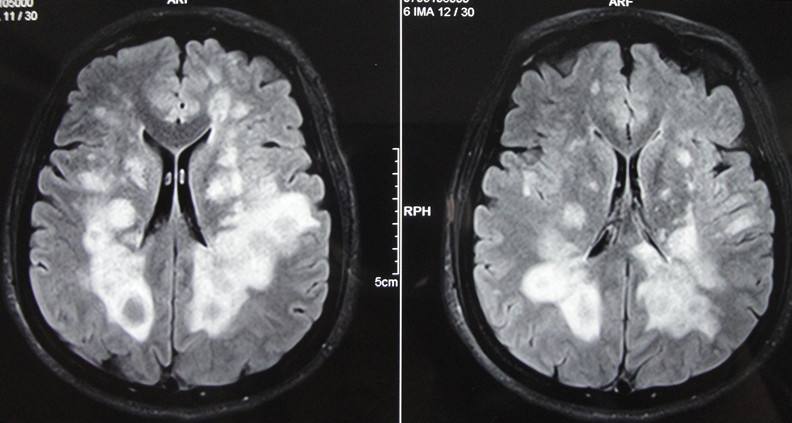

患者,男,李XX,41歲,家住本市,該患于入院前2年,無明顯誘因出現(xiàn)右側(cè)肢活動不靈,表現(xiàn)為走路時腿拖拽,伴有言語不利,尚可與人交談,在“吉林大學(xué)第一醫(yī)院二部”行頭部MRI及腰椎穿刺檢查后診斷為“脫髓鞘病”,治療后好轉(zhuǎn)出院,20天前患者癥狀加重,并伴有左側(cè)肢活動不靈,癥狀無緩解,未予任何治療來我院就診,病程中患者有視物雙影,飲食、睡眠尚可,尿便正常。查體:體溫36.5℃,脈搏71次/分,呼吸18次/分,血壓140/80mmHg,神志清楚,言語不利,查體合作,計算力、記憶力、定向力、理解力、判斷力正常,雙側(cè)額紋對稱,雙側(cè)瞳孔等大同圓,直徑約3.0mm,對光反射靈敏,雙眼各向運動正常,無眼球震顫,無鼻唇溝變淺,伸舌居中,懸雍垂居中,雙側(cè)咽反射靈敏,右側(cè)肢體肌力3級,左側(cè)肢體肌力4級,肌張力增高,膝腱反射亢進,雙側(cè)Babinski征(+),頸無抵抗 ,雙側(cè)Kernig征(-),昂伯士征(+),雙側(cè)肢體深、淺感覺未見異常,雙肺呼吸音清,心率71次/分,節(jié)律規(guī)整,各瓣膜聽診區(qū)未聞及雜音,腹平軟,無壓痛,肝脾肋下未觸及,雙下肢無浮腫。入院后行頭部、頸椎、胸椎MRI:脫髓鞘病病史: 雙側(cè)側(cè)腦室后角、下角旁、放射冠及半卵圓中心、胼胝體見片狀及團塊狀異常信號影,T1WI呈低信號,T2WI及FLAIR呈高信號;各腦室、腦池大小形態(tài)未見明顯異常,中線結(jié)構(gòu)居中,矢狀面掃描示垂體大小形態(tài)正常。彌散成像腦質(zhì)未見明顯異常高信號影。頸椎生理曲度變直,部分椎體邊緣骨質(zhì)增生。C3/4、C4/5、C5/6間盤向后方局限性突入,硬膜囊前緣受壓。黃韌帶未見明顯增厚。頸髓未見明顯異常信號影。 胸椎生理曲度尚可,椎體骨質(zhì)結(jié)構(gòu)完整。各胸椎間盤未見明顯突出或膨出,黃韌帶無增厚。約T2、5、12椎體水平脊髓內(nèi)見條片狀長T2信號影。心電圖示:竇性心律,心率71次/分,大致正常心電圖。此次考慮患者脫髓鞘病復(fù)發(fā),經(jīng)過吉大一院劉群教授會診后,給予激素大劑量沖擊治療,病程中激素逐漸減量,經(jīng)過一個療程的治療,患者癥狀較前明顯好轉(zhuǎn),肢體活動較前靈活,患者滿意的出了院。